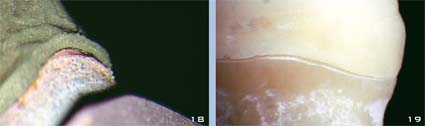

Oft ist es schwierig, Ästhetik und Präzision gleichzeitig zu erzielen. Häufig wird eher die Ästhetik angestrebt als die Präzision oder umgekehrt. Vertreter der Ästhetik behaupten oft, dass für die Gesundheit des Parodonts gar keine exzessive Präzision erforderlich sei. Die Anhänger der Präzision preisen dagegen die Tugenden von Gold, dem einzigen Material, das präzise Ränder garantieren kann (Abb. 18 und 19).

Abb. 18 und 19 Randspalt bei einer Metallkrone (18) und einer Vollkeramikkrone ohne verstärkenden Core (19). Diese Unvollkommenheit ist so gering, dass sie mit Zement ausgefüllt werden kann. Allerdings ist der Zement dem Speichel ausgesetzt, was kurz- oder mittelfristig zu einem Misserfolg führen kann, je nach Zementierungstechnik und -material.